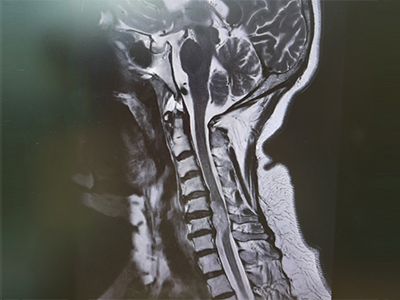

脊柱脊髓神经微创中心以微创技术为引领,以功能恢复为目标,主要治疗脊柱外伤、肿瘤、退行性病变、脊柱畸形等疾病。团队利用神经外科显微技术,结合神经内镜微创技术,对脊柱间盘变性疾病、颈腰椎管狭窄、颈腰椎间孔狭窄、颈腰椎间盘突出、颈腰椎体不稳、脊柱骨折、寰枢椎脱位、脊柱肿瘤、椎管内肿瘤、脊髓损伤、脊髓空洞、脊髓栓系等疾病进行高效、特色手术治疗,如颅颈交界区畸形寰枕减压内固定术、脊柱肿瘤全脊椎切除内固定术、微创椎管内肿瘤切除术、微创脊柱旁肿瘤切除术、寰枢椎脱位椎间融合内固定术、脊柱骨折微创经皮椎弓根钉内固定术、经椎间孔椎间融合内固定术(MIS—TLIF)等,最大程度降低脊柱脊髓手术创伤,具有创伤小、输血少、恢复快、口碑好,出院早等优势。